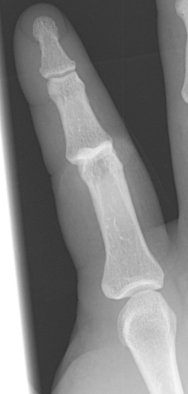

Return to Coach' s Finger